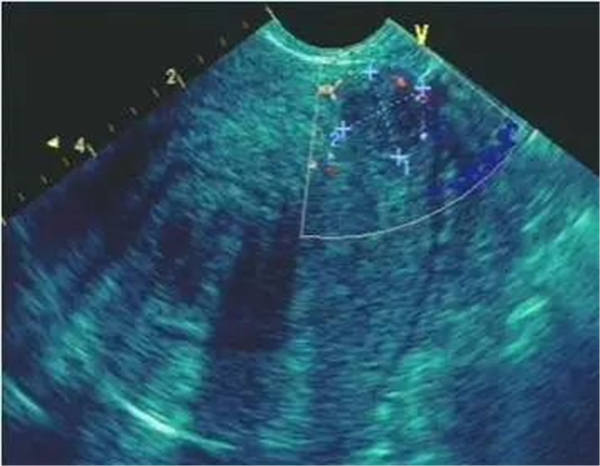

作為最特異的超聲心動圖特征,當右室/左室前后徑比值 > 0.5;右室/左室橫徑(右房/左房橫徑)比值 >1.1或者左心室收縮末期和舒張末期徑均減小,尤以舒張末期為著時,即可判定血栓性肺栓塞癥。

右室壁運動幅度減低

正常情況下,右室前壁運動幅度應>5 mm,右室游離壁運動幅度會>8 mm,但對肺栓塞(PTE)患者,右室壁基底部至游離部運動幅度減低,甚至消失。